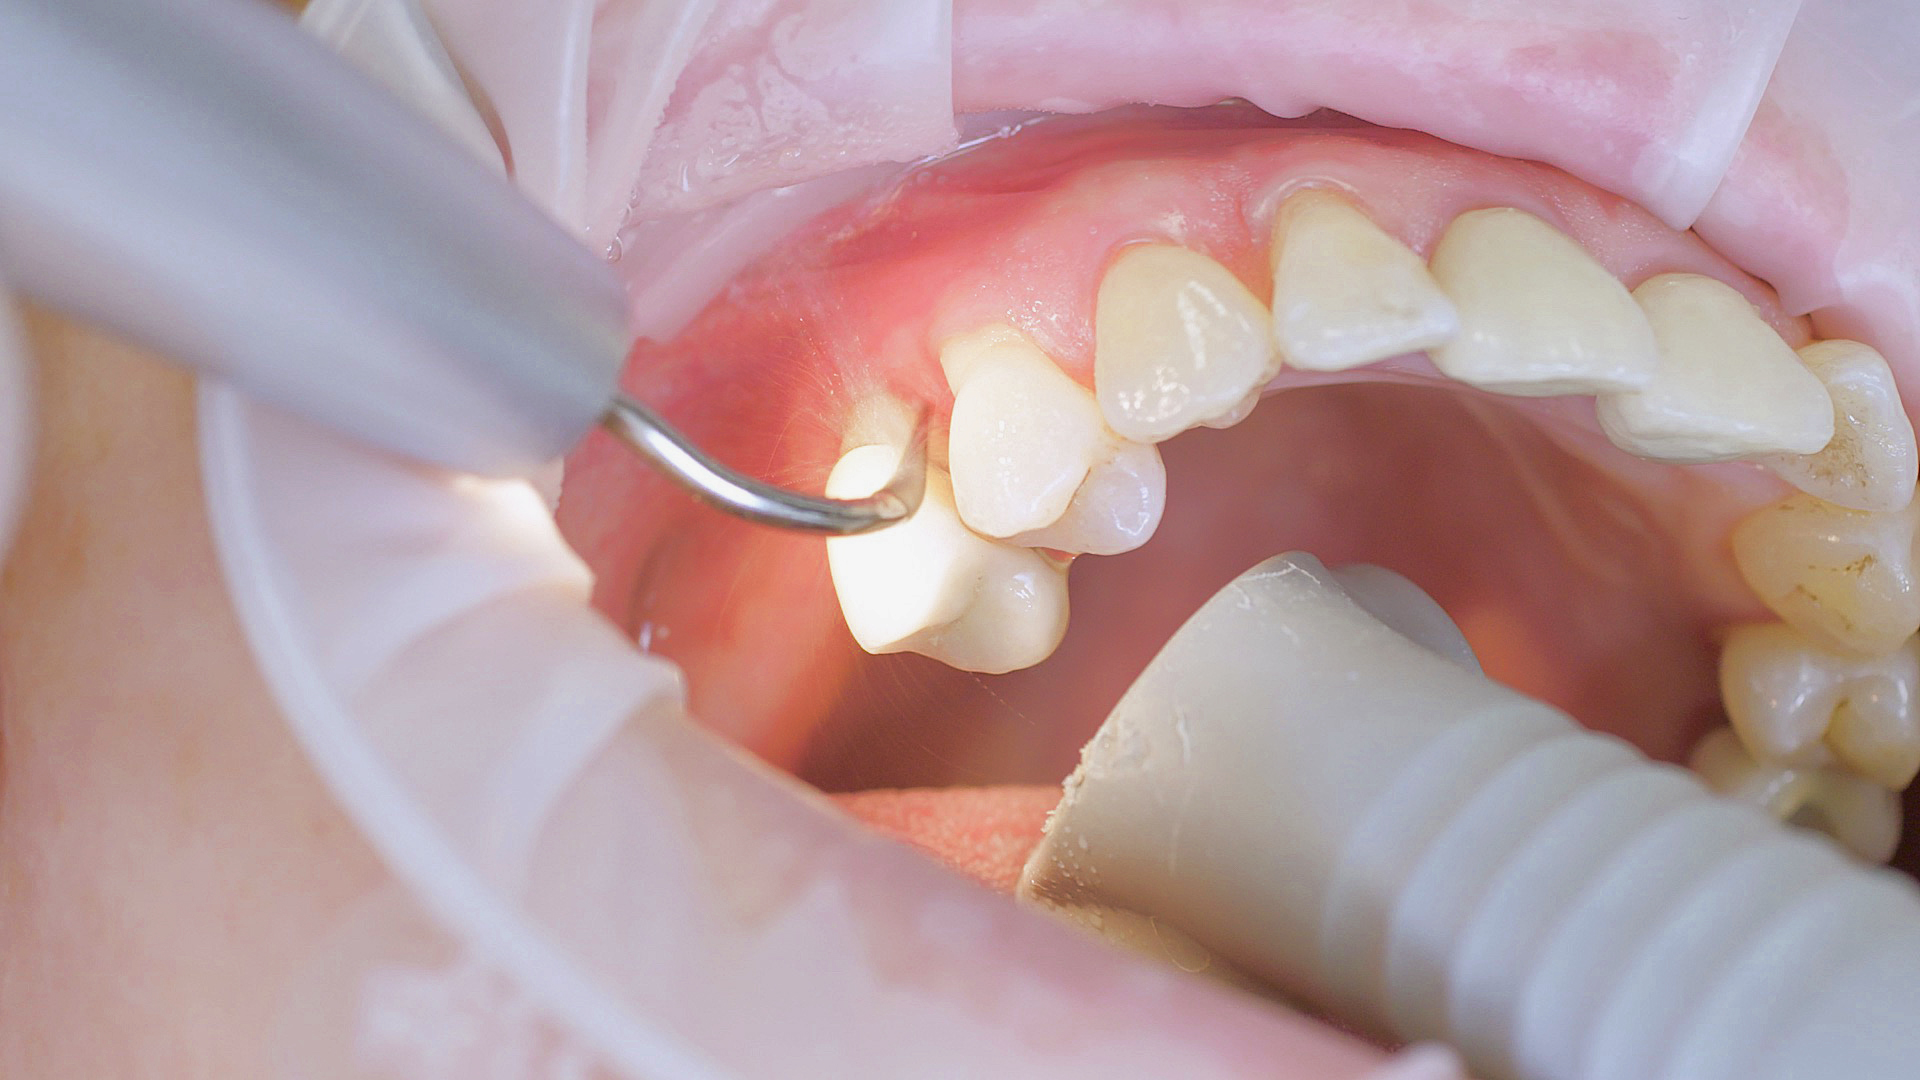

Dans le cadre du traitement parodontal préventif, le détartrage subgingival (debridement en anglais) est effectué à l'aide d'appareils à ultrasons et d'inserts paro spécifiques (Fig. 3). Des instruments manuels peuvent également être utilisés. En fonction de la situation, d'autres mesures, y compris chirurgicales et régénératives, peuvent s’avérer nécessaires.